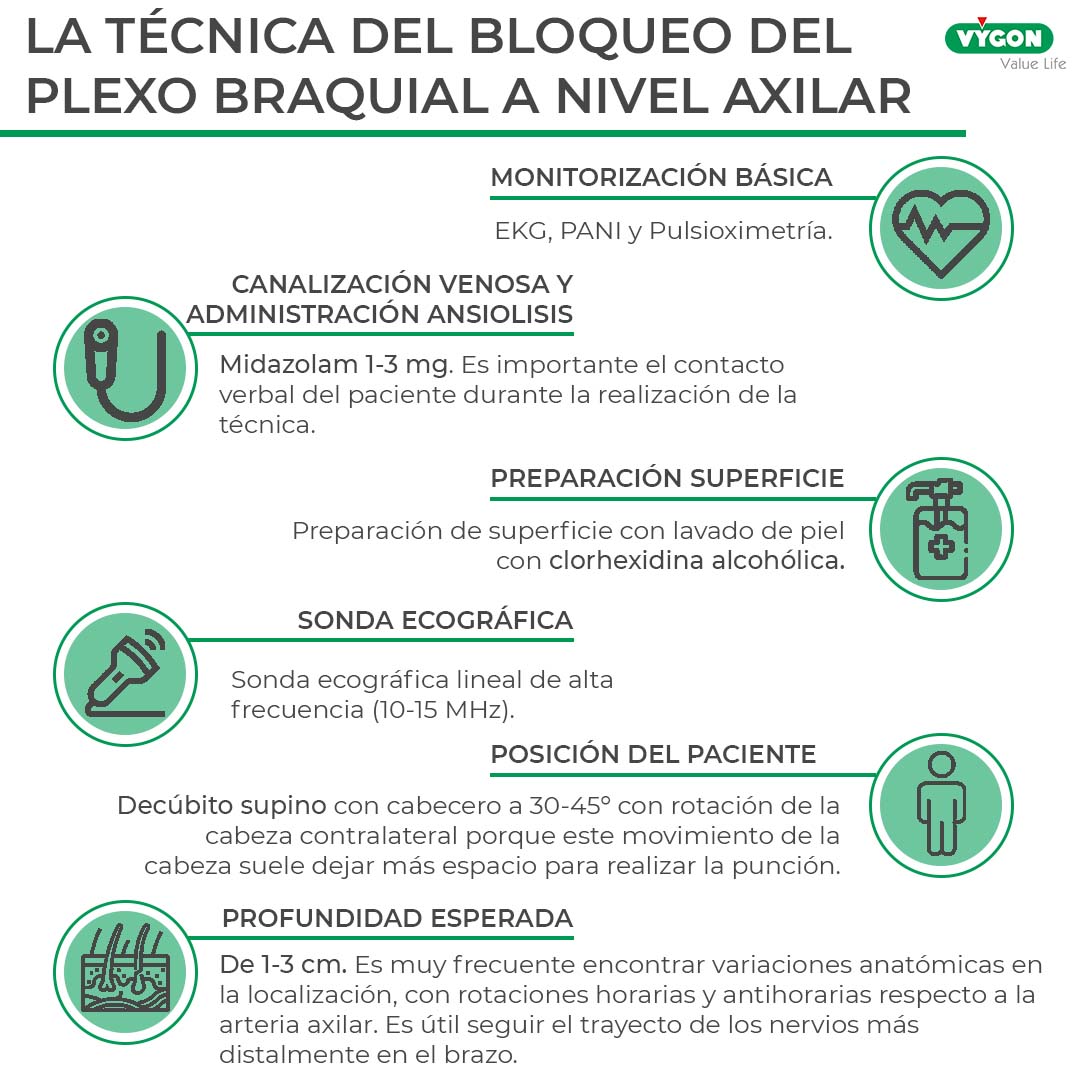

Técnica del bloqueo del plexo braquial a nivel axilar

- Monitorización básica: EKG, PANI y Pulsioximetría

- Canalización de vía venosa y administración de ansiolisis ligera: Midazolam 1-3 mg. Es importante mantener el contacto verbal del paciente durante la realización de la técnica.

- Preparación de superficie con lavado de piel con clorhexidina alcohólica.

- Sonda ecográfica lineal de alta frecuencia (10-15 MHz)

- Posición del paciente: decúbito supino con cabecero a 30-45º con rotación de la cabeza contralateral porque este movimiento de la cabeza suele dejar más espacio para realizar la punción.

- Profundidad esperada de 1-3 cm. Es muy frecuente encontrar variaciones anatómicas en la localización, con rotaciones horarias y antihorarias respecto a la arteria axilar. Para facilitar su visualización ecográfica es útil seguir el trayecto de los nervios más distalmente en el brazo.